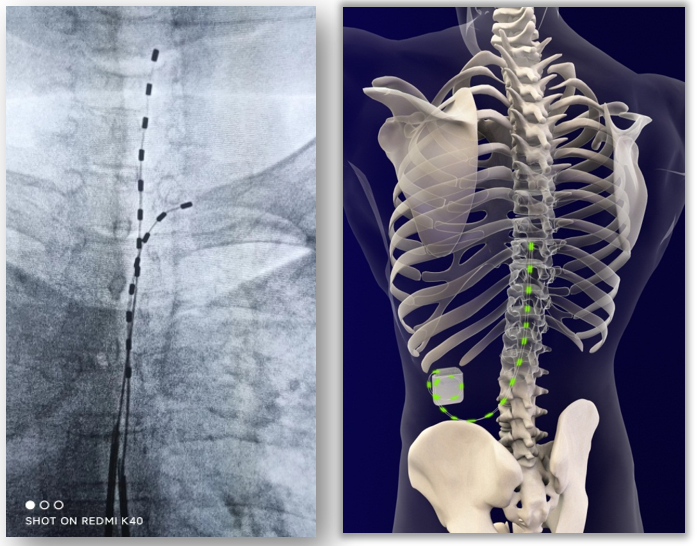

髓电刺激疗法是将电极植入脊柱椎管内,以脉冲电流刺激脊髓神经治疗疾病的方法。通过植入体内的起搏器系统发放弱电脉冲至脊髓,阻断疼痛信号经脊髓向大脑传递,从而有效缓解顽固性神经性疼痛,使病人恢复身体机能,有效提高生活质量。该技术具有创伤小、操作简便、患者效果反馈好的特点,主要适用于带状疱疹后遗神经痛、慢性顽固腰腿痛、神经损伤后疼痛(手术后神经痛,包括:臂丛神经损伤痛、截肢后幻肢痛及残肢痛)、外周缺血性疼痛(糖尿病性肢体疼痛、雷诺氏病、伯格氏病、血栓闭塞性脉管炎)等。